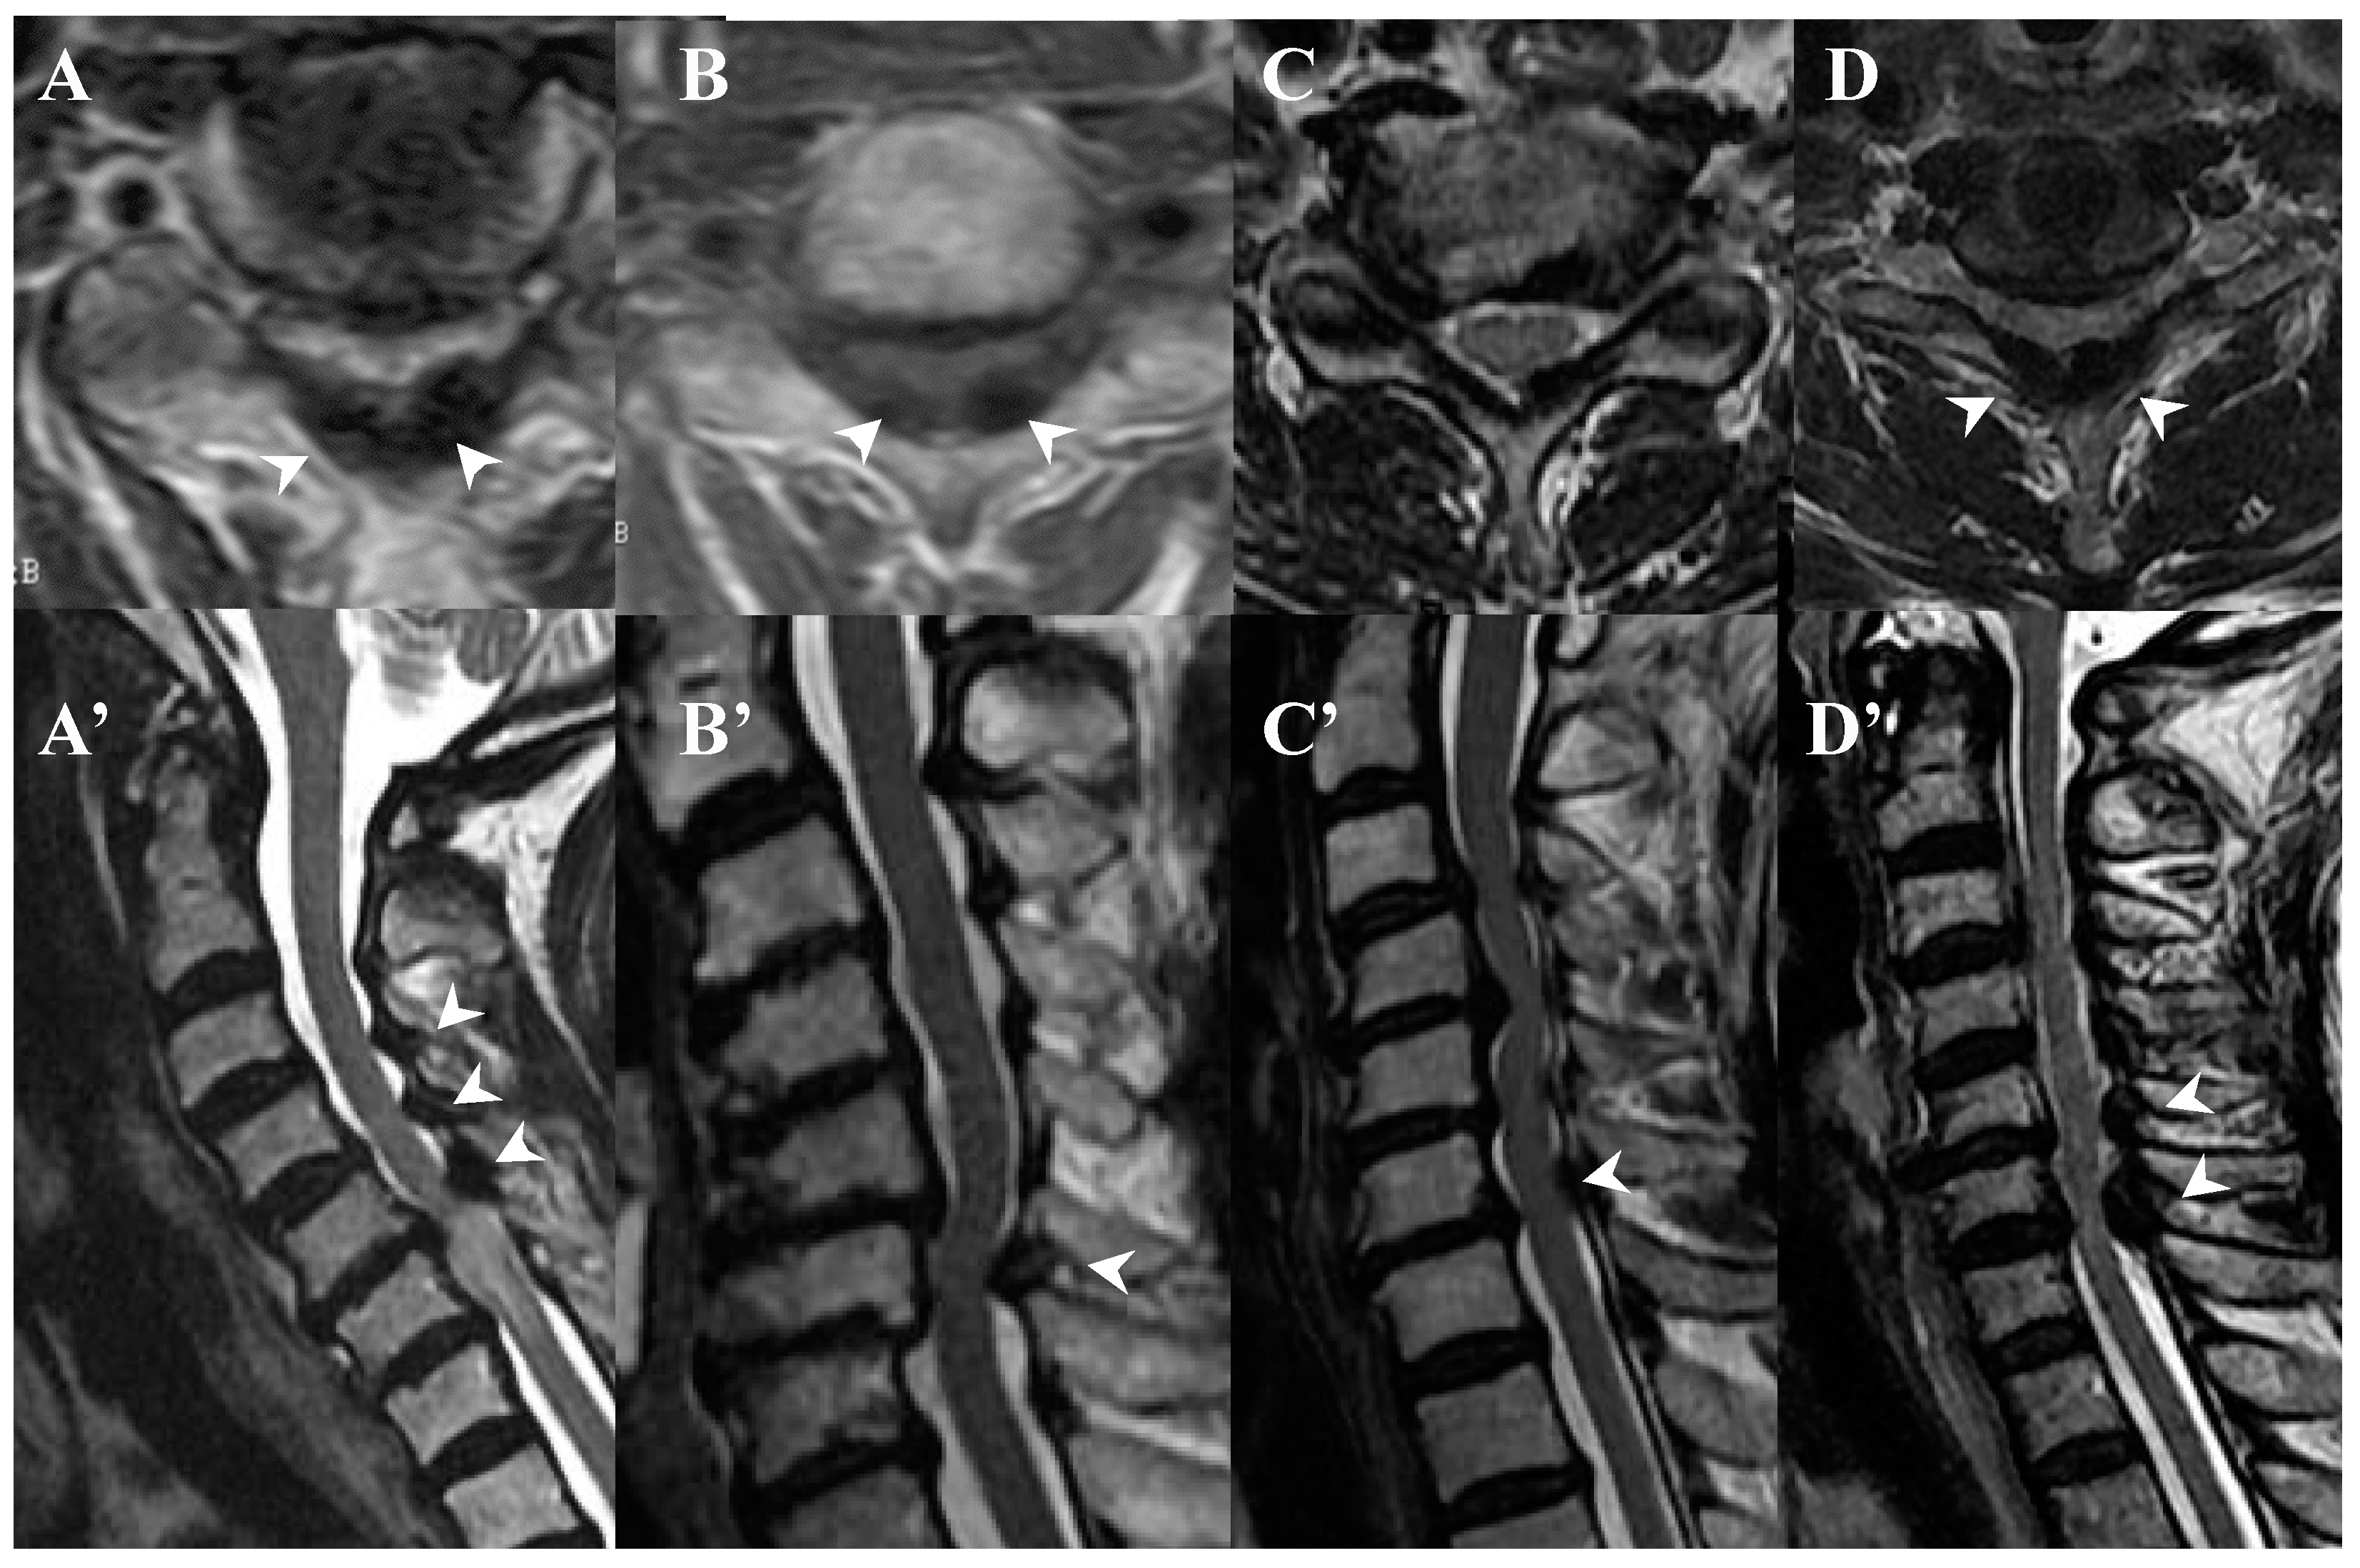

3.3. Neuroradiological Findings (Figure 3, Figure 4, Figure 5 and Figure 6; Table 3)

CLF: All cases exhibited spondylotic changes. Developmental narrowing (anterior-posterior diameter of spinal canal < 12 mm) of the spinal canal was observed in five cases, disc herniation in four cases, and ossification of the longitudinal ligament in three cases. Two-dimensional (2D)-reconstructed CT images demonstrated “multiple islands of speck-like and egg-shaped” high-density mass, “diffuse and speck-like” high-density masses, and/or “egg-shaped” high-density masses in the ligamentum flavum (Figure 3). In three cases, there was ossification of the longitudinal ligament (Table 3). MR T2-weighted images showed these mass lesions as areas of low intensity or isointensity, with compression of the spinal cord. The presence of both low-intensity and isointense regions suggested a combination of calcification and ligamentum tissue (Figure 4). In five cases, dynamic X-rays of the cervical spine demonstrated instability of joints (Table 3).

Figure 4.

MR images of CLF. MR T2-weighted axial images (A–D) and sagittal images (A’–D’) from the same patient showing low intensity (arrow heads).

OLF: There were spondylotic changes in 17 cases, developmental narrowing of the spinal canal in 7 cases, disc herniation in 7 cases, ossification of the longitudinal ligament in 4 cases, diffuse idiopathic skeletal hyperostosis (DISH) in 4 cases, and ankylotic spinal hyperostosis (ASH) in 3 cases [31,51,52]. Two-dimensionally reconstructed CT images showed beak-like ossification extending into the intervertebral foramen (Figure 5) (Table 3). MR T1-weighted and T2-weighted images demonstrated low-intensity masses in the dorsal spinal canal, which compressed the spinal cord. In some cases, there were high-intensity spots, suggesting the formation of bone marrow (Figure 6). In three cases, dynamic X-rays of thoraco-lumbar spine demonstrated joint instability (Table 3).

Figure 6.

MR images of OLF. MR T1-weighted axial images (A–D) and T2-weighted axial images (A’–D’) demonstrating low-intensity mass in dorsal spinal canal compressing spinal cord (arrows) and high-intensity spots (white asterisks).

4.2. Comparison of Neuroradiological Findings between CLF and OLF (Figure 3, Figure 4, Figure 5 and Figure 6; Table 3)

CLF: A two-dimensionally reconstructed CT scan revealed “multiple islands of speck-like and egg-shaped” high-density mass and/or “diffuse and speck-like” high-density mass within the ligamentum flavum. MR T1- and T2-weighted images depicted these mass lesions as low intensity or isointense, with compression of the spinal cord. The presence of low-intensity and isointense regions suggested a combination of calcified regions and ligamentum tissue (Table 3, Figure 1 and Figure 2) [3,4,6,7,9,10,12,14,15,17].

OLF: Two-dimensionally reconstructed CT scan images showed beak-like ossification extending into the intervertebral foramen. MR T1-weighted and T2-weighted images demonstrated a low-intensity mass within the dorsal spinal canal compressing the spinal cord. In some cases, the presence of high-intensity spots suggested bone marrow formation (Figure 3 and Figure 4) [18,26,29,30,31]. In some cases, OLF was associated with DISH and ASH, indicating a more generalized ossification pattern (Table 3). Previous reports have reported the association of DISH and ASH in OLF, but the specific features of this association were unclear [51,52]. In both CLF and OLF, spondylotic changes were the most common associated condition, followed by disc herniation and instability. This suggested that chronic micro-movement and mechanical stress (traction, rotation, and compression) to the ligament were contributing factors (Table 3).